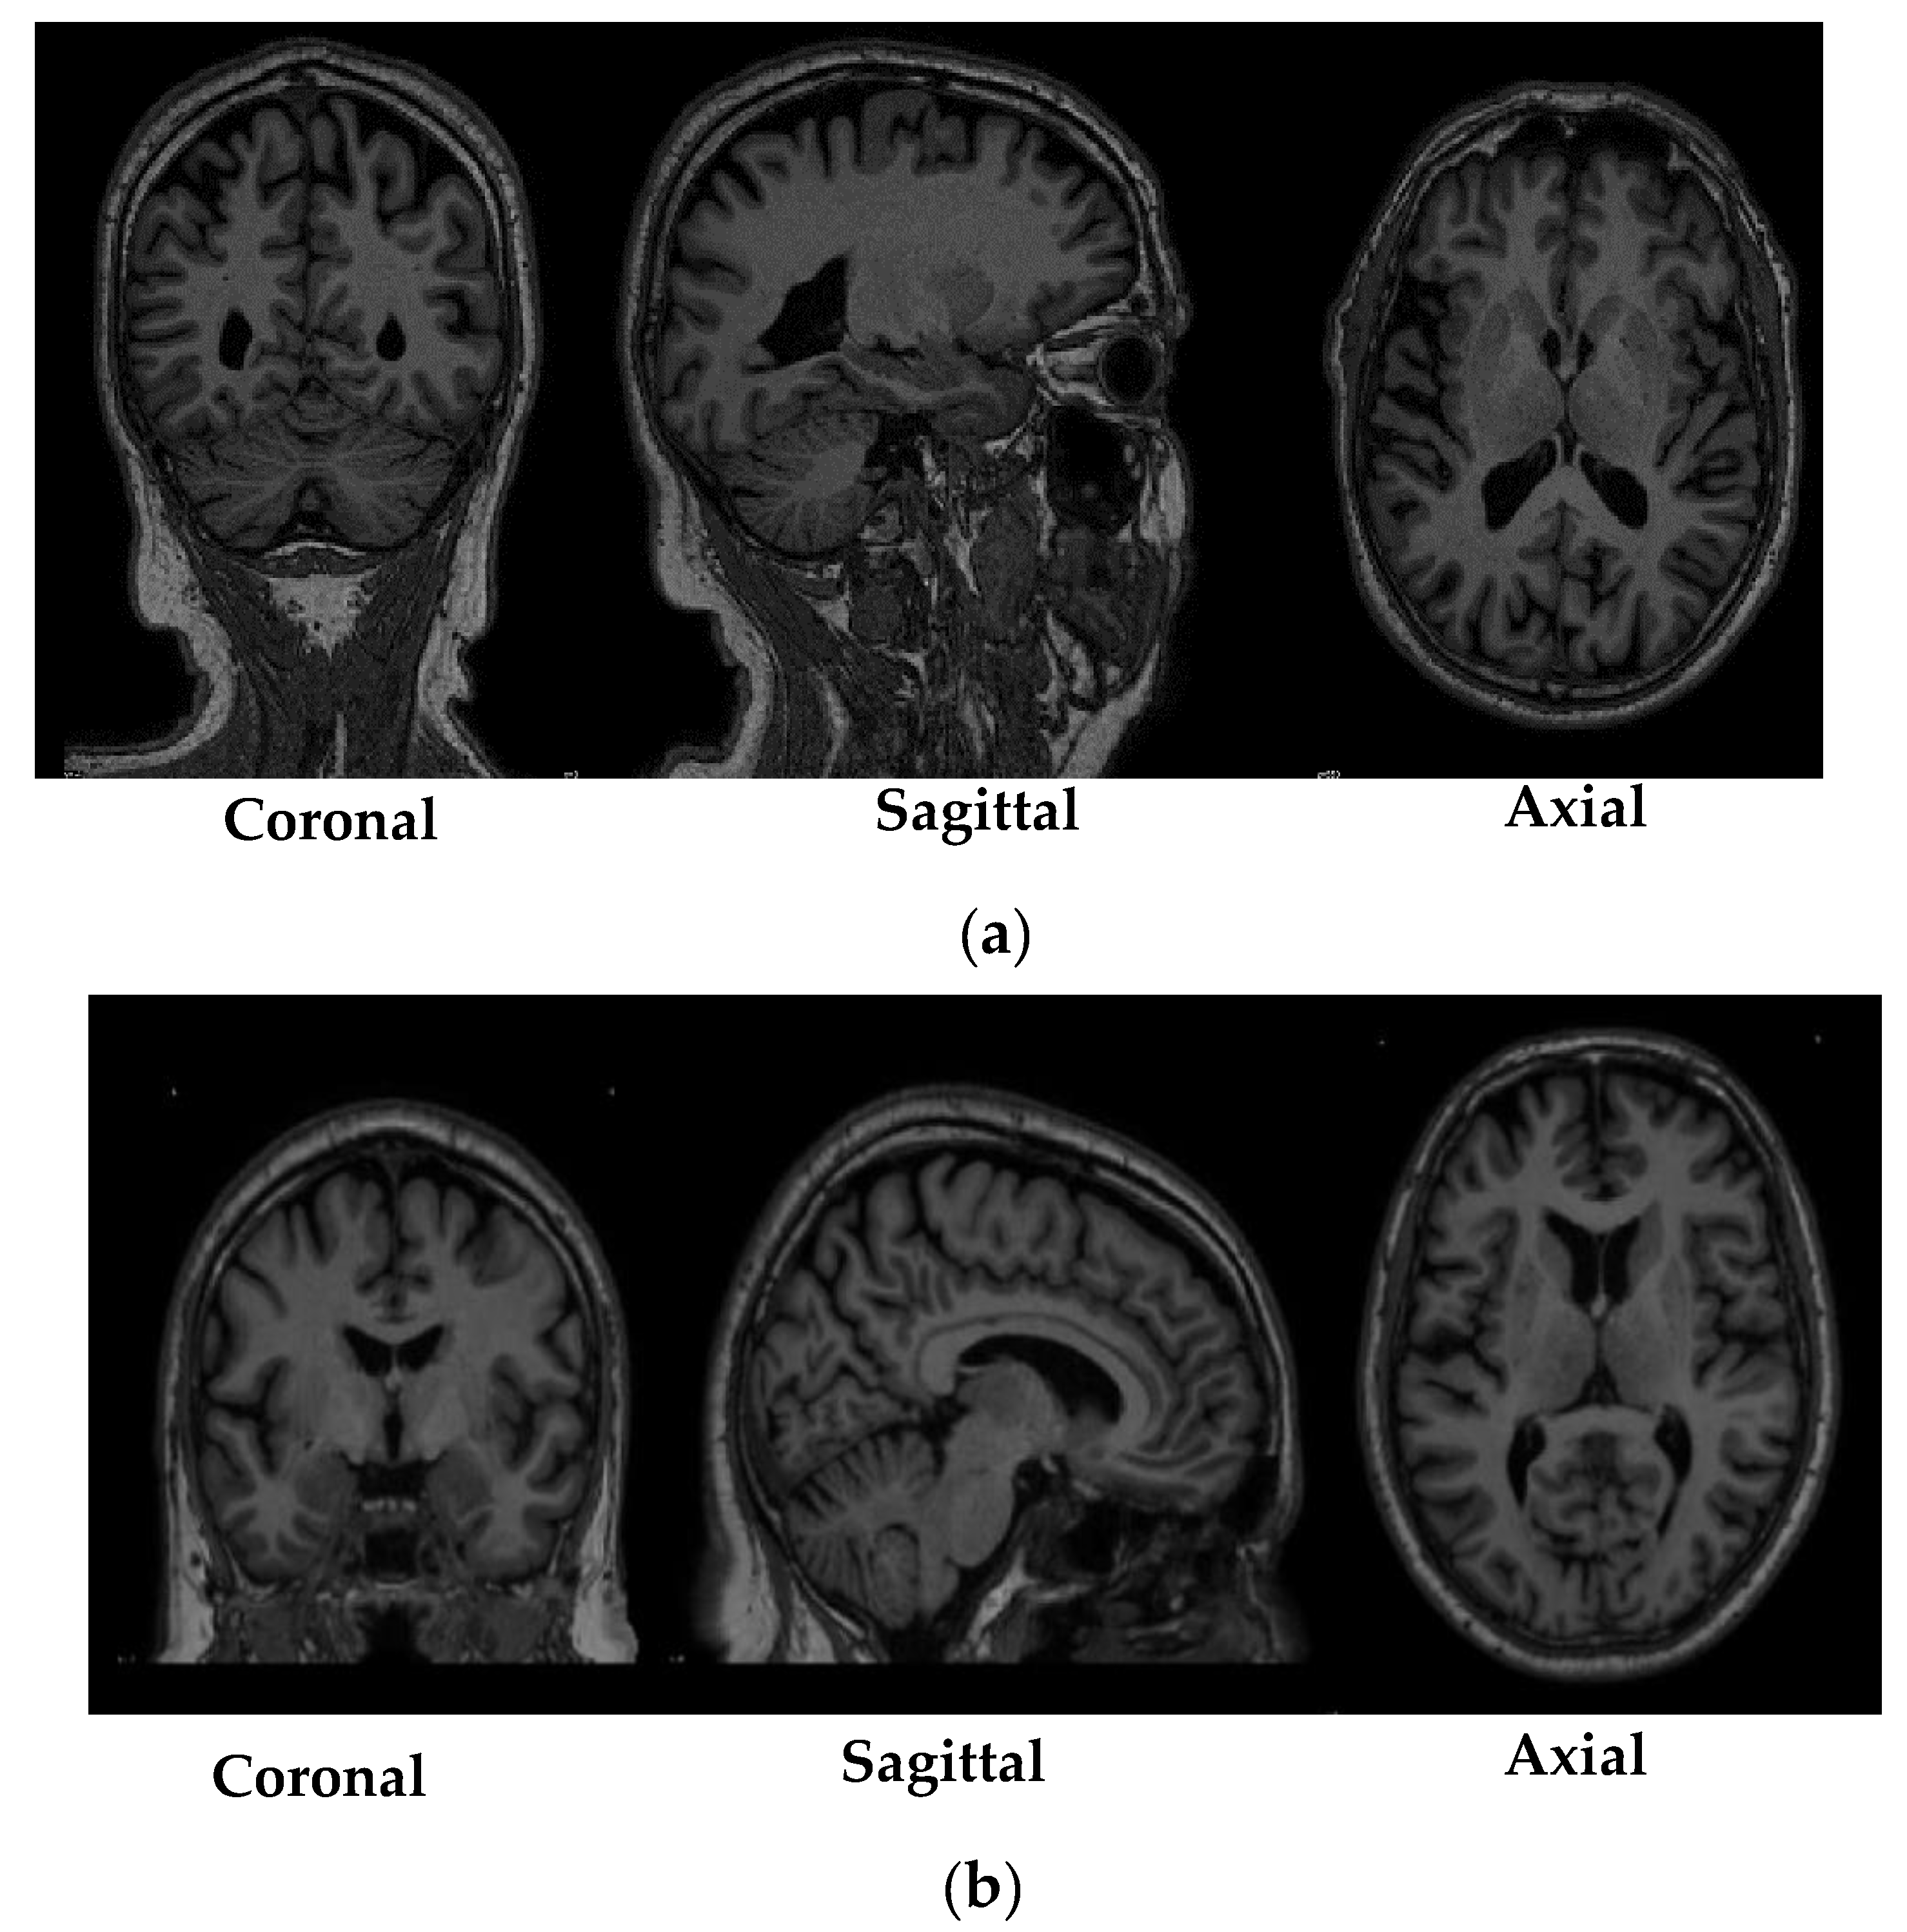

From www.mdpi.com

Diagnostics Free FullText Detection of Parkinson’s Disease from 3T T1 Weighted MRI Scans Scan Test For Parkinson Disease there is no lab or imaging test that is recommended or definitive for parkinson’s disease. diagnosing parkinson's disease is difficult, especially early in the disease. While the patient with a classical presentation of parkinson’s disease, such as unilateral rest tremor and shuffling gait, can be. there is no specific test for diagnosing parkinson’s disease. Food and drug. Scan Test For Parkinson Disease.